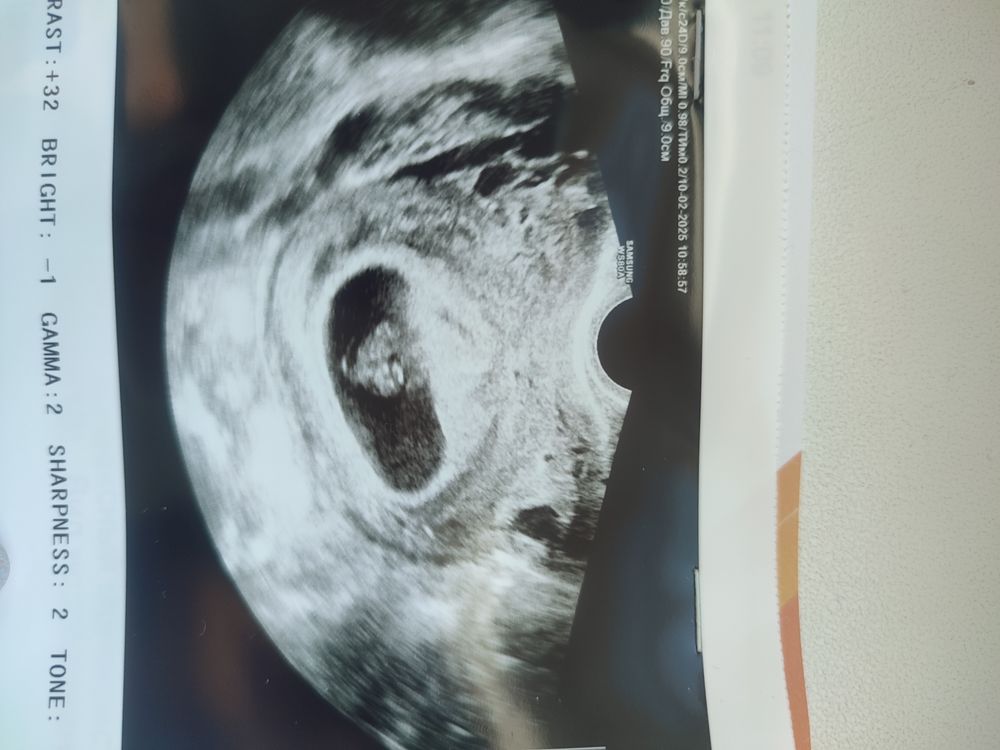

Фух🙏Ровно 8 недель🫶Кто рядом, делитесь🤗

Мы 😁 8 недель и 4 дня 🤗

У меня 8.1. Сегодня тоже была на узи. Ктр 17.3 мм